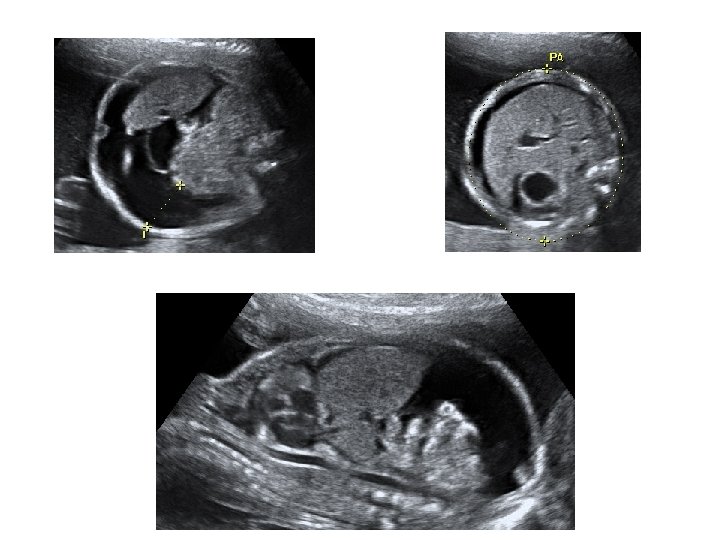

Échographie du 2ème trimestre • Entre 21 et 23 SA • Évaluer la croissance fœtale - pôle céphalique BIP : diamètre bipariétal PC : périmètre céphalique - abdomen fœtal CA : circonférence abdominale - extrémités : LF : longueur fémorale

• Étude morphologique approfondie - pôle céphalique : contours de la boite crânienne, volume des ventricules latéraux, structures de la ligne médiane, cervelet (aspect et mesure de sa largeur) - distance inter-orbitaire - coupe nez-lèvre - profil : menton aligné avec le front, mesure des OPN

- thorax : cœur (position, 4 cavités équilibrées, septum inter ventriculaire, croisement Ao/AP), poumons - abdomen : paroi intègre, estomac (position, volume), vésicule biliaire, intestin grêle - arbre urinaire : vessie (position, volume), 2 reins - sexe - rachis avec son revêtement cutané - membres : 4 x 3 segments, 5 doigts aux 2 mains, mouvements d’ouverture des mains, mesure du pied